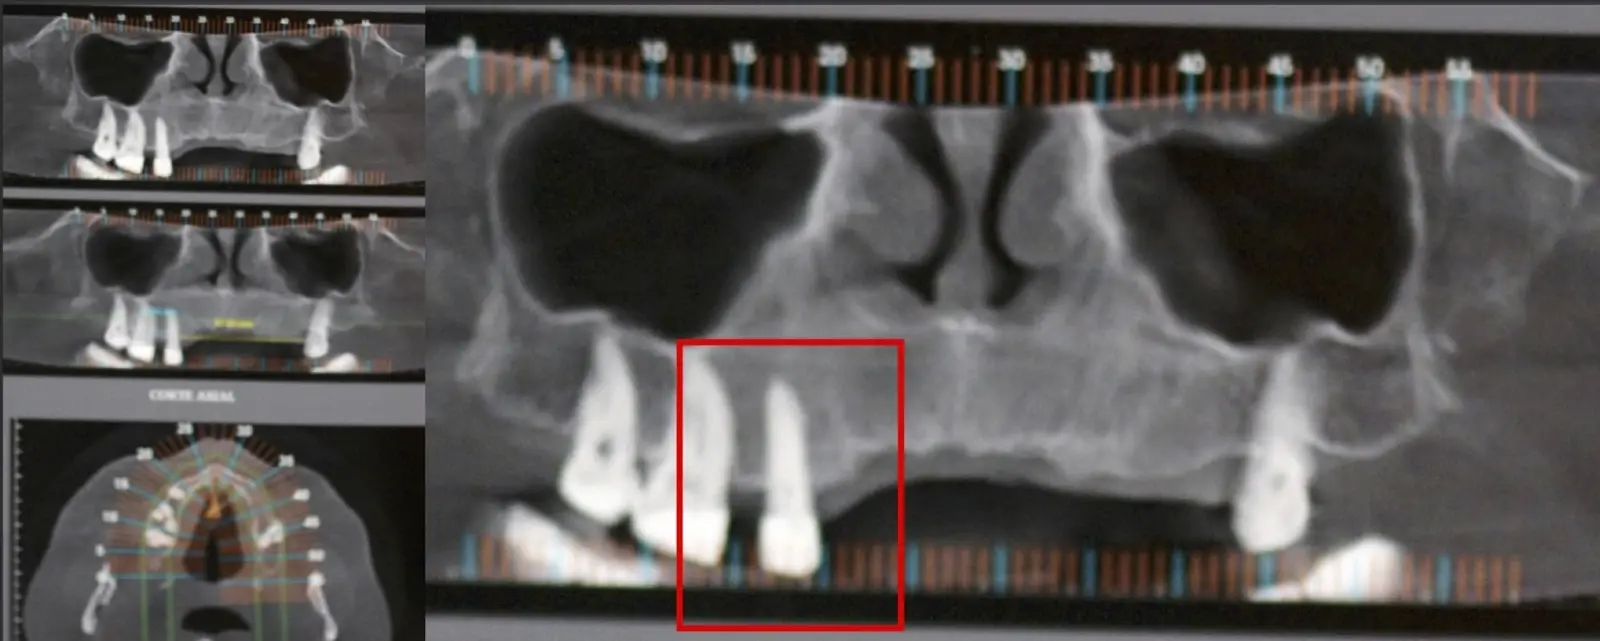

El origen puede ser bacteriano (colonias bacterianas persistentes4, patología periodontal asociada5, reinfecciones por falta de sellado coronal), mecánico (preparación deficiente, fractura de instrumentos, fracturas radiculares6, extravasación de material de obturación7 con ó sin compromiso de estructuras vecinas) y anatómico (conductos accesorios poco permeables o calcificados)8 (Figuras 1 - 4).

La microcirugía endodóntica apical busca conservar la mayor cantidad de longitud de raíz y de hueso circundante sano para no afectar la estabilidad de la pieza.11 Por ello, es ideal el uso de microscopios, elementos de magnificación, instrumental específico (insertos de ultrasonido endodónticos) y materiales de sellado eficientes para el tratamiento retrogrado. Su éxito es alto y evidencia una cicatrización ósea completa en el 74% de los casos al año de tratamiento.12 Cabe destacar que este logro está asociado también, a predictores propios de cada paciente, como la edad, tipo de pieza, profundidad de sondaje y extensión de la lesión.1 El uso complementario de la tomografía computarizada es resaltante como el instrumento imagenológico de elección para la etapa de planificación microquirúrgica,13 ya sea para una ejecución a mano alzada o con guías prefabricadas.14,15

El procedimiento se inicia colocando anestesia y elevando un colgajo mucoperióstico a espesor completo3 (incisión semilunar o intrasurcular con/sin protección papilar) y exponiendo la zona. En seguida se realiza la enucleación de la lesión, eliminando16 o creando una ventana17 en la lámina cortical que contiene el área del ápice; este retiro óseo se realiza con los insertos de forma aplanada dentada o inserto con cobertura diamantada plano o redondo, recordando ser lo más conservador posible (Figura 5).